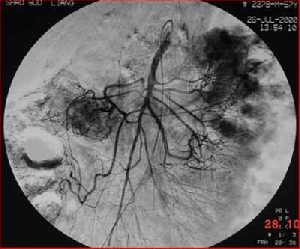

腸癌治療新選擇——介入+手術

有這么一種對付腫瘤的辦法:一方面將高濃度的藥物直接作用于局部,發(fā)揮最大的抗腫瘤作用,對全身毒副作用小,絕大部分患者能接受治療;另一方面,可將腫瘤的供血血管阻塞,